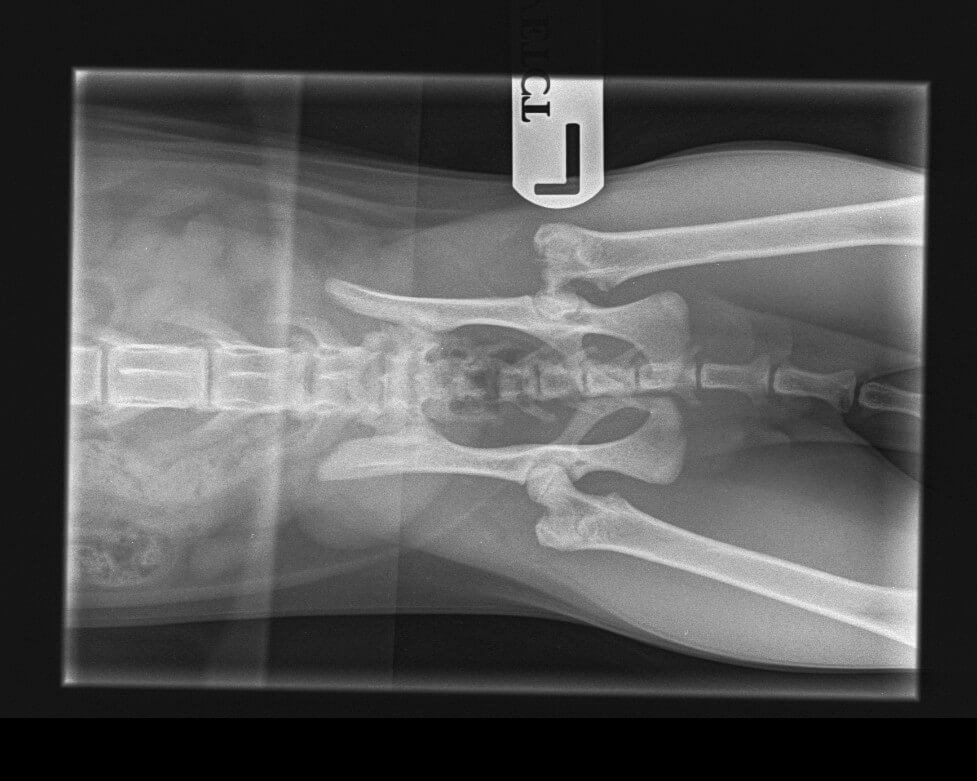

X-rays revealed a shocking sight. Cleo’s left hip joint was disintegrating and almost non-existent. The vet confirmed a diagnosis of Legg-Calvé-Perthes Disease.

This is a rare, degenerative condition caused by a lack of blood flow to the femoral head (the “ball” of the hip joint), leading to bone death (necrosis). It typically affects young cats in their first year and, as Cleo’s owners discovered, it isn’t caused by an injury…it simply happens.

To give Cleo a life without pain, the vets recommended a Femoral Head and Neck Excision (FHNE) which is a surgery to remove the damaged part of the joint.